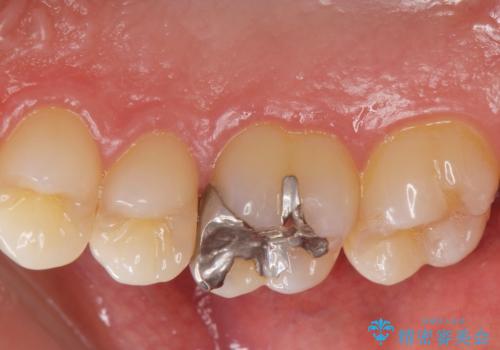

- 銀歯を白くしたいとの事で来院。

銀歯を除去し拡大鏡下でカリエスがない事を確認した後、e-maxインレーにて治療を行いました。